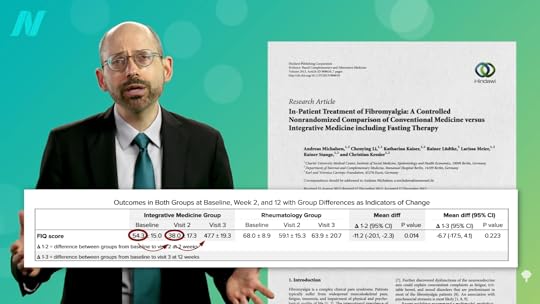

A similar success story was reported with fibromyalgia. A woman with pain throughout her body, who couldn’t sustain activity and was on a lot of drugs, became “symptom-free” after a 24-day fast and remained that way at her “follow-up visit 1 month later.” However, when a modified fasting regimen was tried on dozens of individuals, the benefits seen at week 2 largely disappeared by week 12, as shown below and at 1:32 in my video Fasting for Autoimmune Diseases.